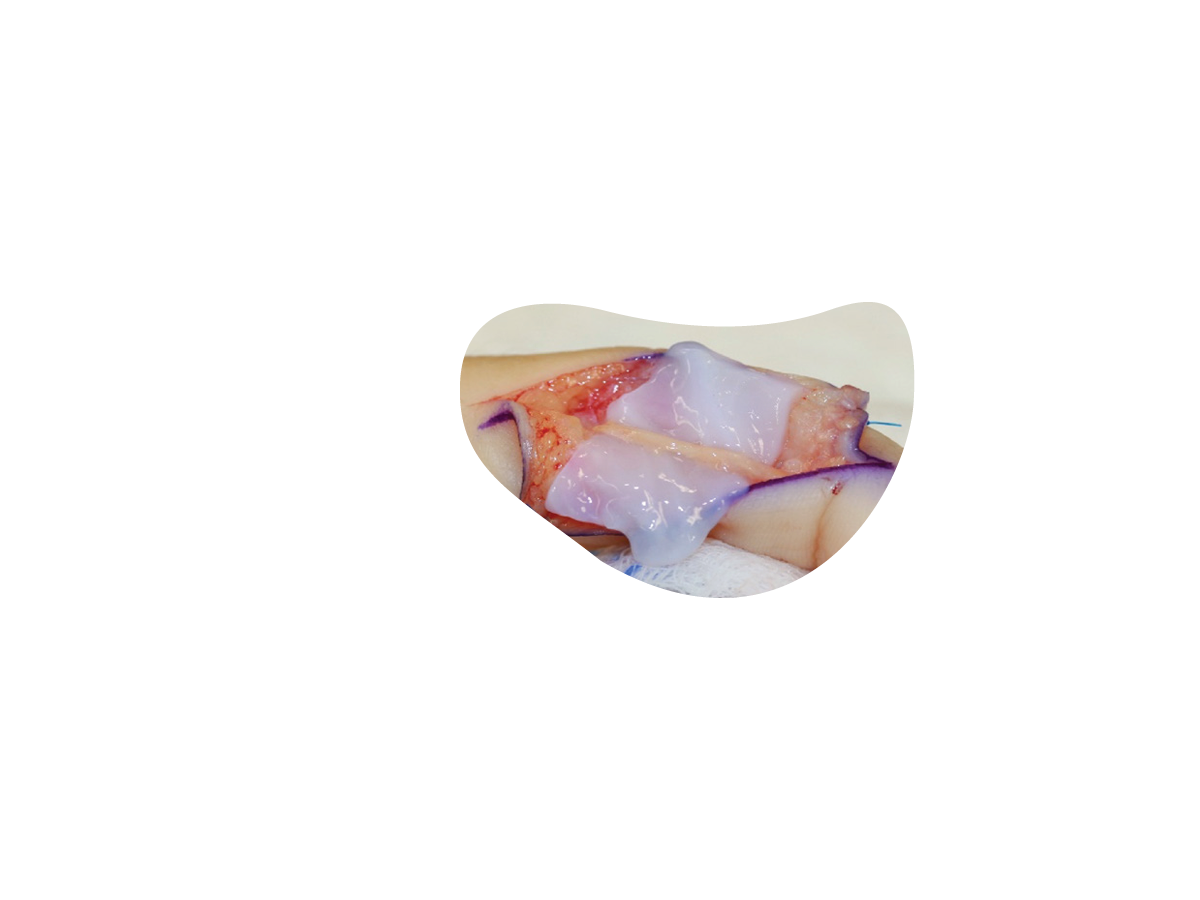

STRAVIX◊ Tissue

Cryopreserved Umbilical Tissue

STRAVIX Tissue is a robust, easy-to-handle graft that sutures easily, conforms intimately, and performs across specialties*, from podiatric wounds to complex soft tissue reconstruction.1

*Can be used as a wrap, cover, or barrier